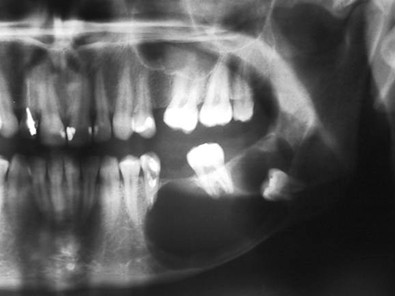

Przedstawiony wynik badania radiologicznego powinien w pierwszej kolejności nasuwać podejrzenie:

Pytanie 79

Pacjent zgłosił się z powodu zniekształcenia twarzy w okolicy trzonu żuchwy. Badanie pantomograficzne ujawniło obecność policyklicznych, osteolitycznych ubytków o ostrych granicach w trzonie żuchwy. Nakłucie chełboczącego wygórowania w przedsionku jamy ustnej wykazało obecność gęstego szaro-białego płynu. Przedstawione objawy mogą przemawiać za:

Pytanie 81

Pacjent zgłosił się z powodu złego samopoczucia, gorączki oraz bólu w okolicy trzonu żuchwy. Badaniem klinicznym stwierdzono powiększenie węzłów chłonnych podżuchwowych, osłabienie czucia wargi dolnej, ponadto ból i rozchwianie zębów po tej stronie. Opisane objawy mogą w pierwszej kolejności nasuwać podejrzenie:

Pytanie 82

Chory odczuwa silny ból zęba promieniujący do otoczenia, ząb jest bolesny przy opukiwaniu i nagryzaniu, nieco rozchwiany. Badanie radiologiczne ujawnia w okolicy wierzchołka korzenia zęba ognisko osteolizy o nieostro zaznaczonych brzegach. Przedstawione objawy mogą przemawiać za:

Pytanie 83

Ognisko rozrzedzenia i osteolizy z otoczką osteosklerotyczną, obecne w badaniu radiologicznym okolicy przyśrodkowych siekaczy może w pierwszej kolejności przemawiać za:

Pytanie 84

Który z wyników badań pozwala rozpoznać torbiel rozwijającą się w kości?

Pytanie 86

W badaniu radiologicznym żuchwy ujawniono obecność ostro ograniczonego jamistego przejaśnienia z tkwiącym zębem, którego korzenie są częściowo zresorbowane. Opisany obraz może w pierwszej kolejności przemawiać za:

Pytanie 87

Badanie radiologiczne żuchwy ujawniło obecność ognisk rozrzedzeń i zagęszczeń struktury kostnej, obraz taki jest charakterystyczny dla:

Pytanie 89

Widoczne na zdjęciu zgryzowym podniebienia ostro ograniczone przejaśnienie o kształcie sercowatym lub gruszkowatym może być podstawą do postawienia rozpoznania torbieli:

Pytanie 101